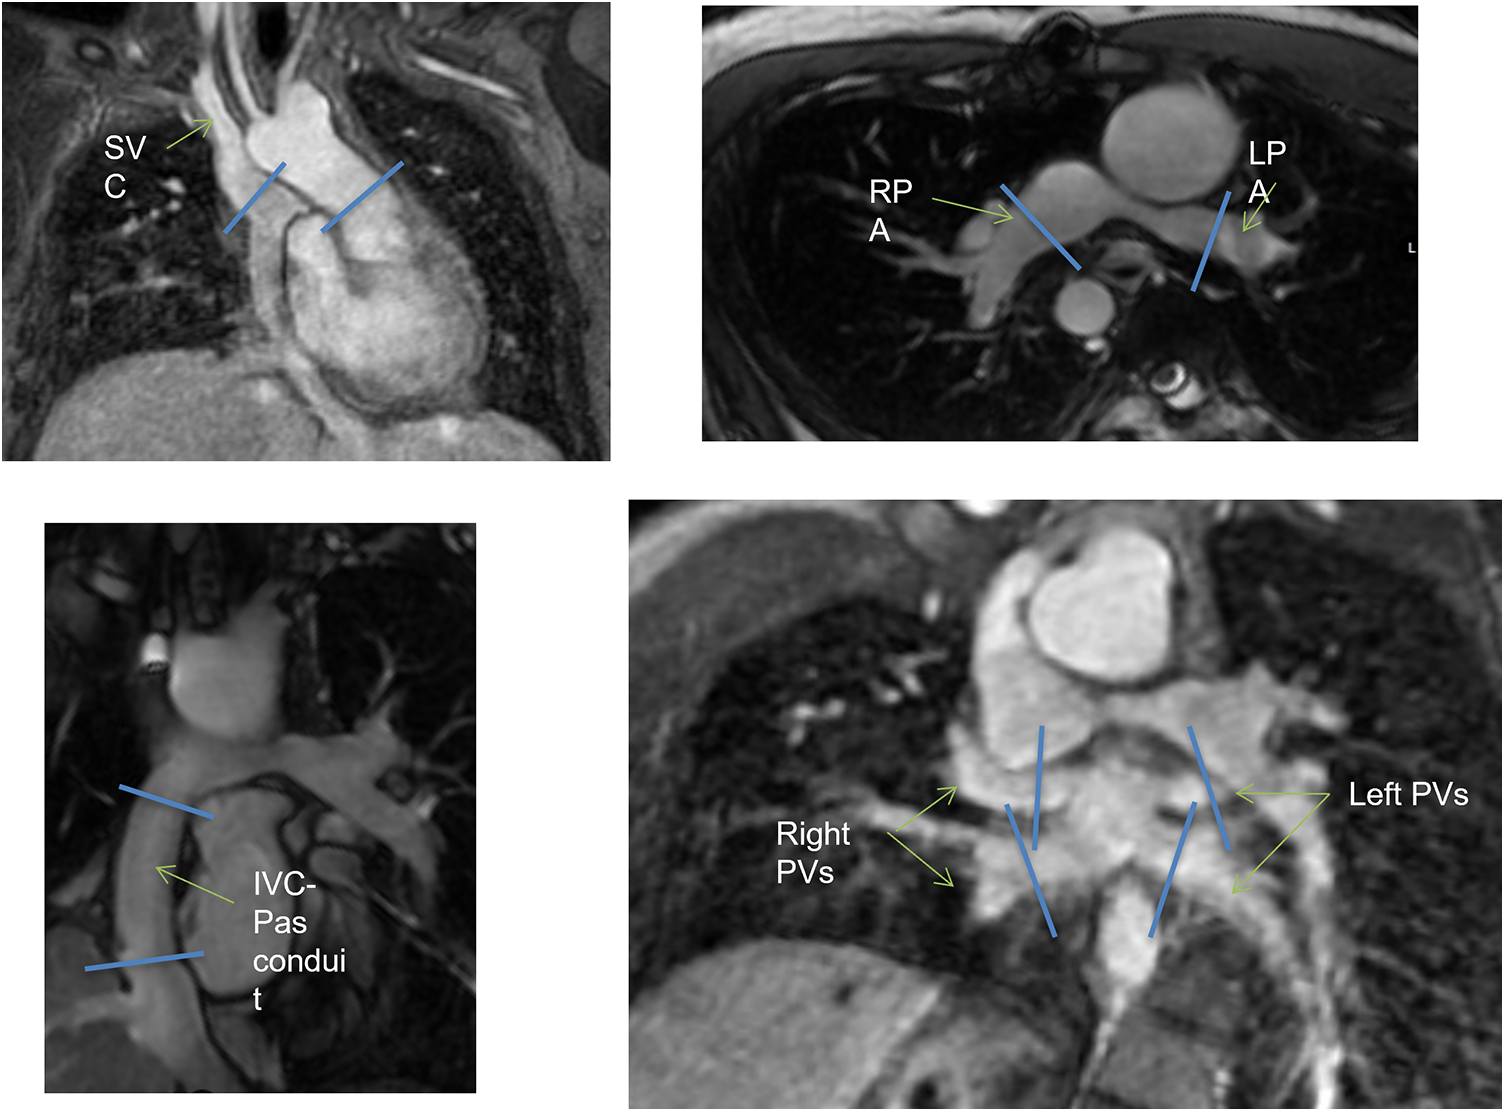

Briefly, functionally single-ventricle short axis was visualized from the base to the apex, using a cardiac cine balanced steady-state free-precession (SSFP) pulse sequence with the following parameters: retrospective ECG gating, field of view 340–360 mm, flip angle 35°–50°, TE 1.4–1.9 ms, TR 2.8–3.8 ms, slice thickness 6–8 mm, slice gap 0 mm, number of signal averages 1–3, reconstructed cardiac phases 30. Several 2D flow scans were performed to evaluate the blood flow in the ascending aorta (Ao), the superior vena cava (SVC), the right pulmonary artery (RPA) and left pulmonary artery (LPA), the individual right and left pulmonary veins (PVs) and the inferior vena cava-pulmonary arteries-conduit/tunnel (abbreviated in the following by IVC-PA conduit) (Fig. 1). The following parameters were used for 2D flow acquisitions: field of view 280–340 mm, flip angle 15°–20°, slice thickness 5–6 mm, view per segment 1–2, number of signal averages 2–4, velocity-encoding (VENC) values 100–450 cm/s depending on the expected blood velocity, reconstructed cardiac phases 30. All 2D flow scans were acquired during free-breathing. The MRI study was completed using a contrast-enhanced (gadopentetate dimeglumine 0.2–0.4 ml/kg). MR angiographic sequence or a time-resolved angiography for the anatomic evaluation of the Fontan pathway. In patients aged <8 years or with incapacity to collaborate the CMR exam was performed on deep sedation using titrated propofol.

images

Figure 1: Schematic illustration of multiple 2D flow prescriptions. IVC, inferior vena cava; LPA, left pulmonary artery; RPA, right pulmonary artery; PA, pulmonary arteries; PVs, pulmonary veins; SVC, superior vena cava

A 4D flow MRI sequence was also prescribed in axial or coronal orientation covering the entire thorax with the following parameters: field of view 250–400 mm, flip angle 8°–15°, TR 3.8–5.3 ms, TE 2.0–3.2 ms, slice thickness 2.2–3.0 mm, in-plane resolution 1.9–3.1 mm, view per segment 1–4, number of signal averages 1–4, VENC 70–150 cm/s, reconstructed cardiac phases 20–32, acquisition time 5–12 min. The SSFP and 2D flow images were elaborated by means of a commercially available software (Mass plus and CV Flow, respectively; version 4.0, MR Analytical Software Systems, Leiden, The Netherlands). Ventricular volumes, mass (indexed to body surface area) and the ejection fraction were calculated. 4D flow MRI data were processed using Arterys Cardio AIMR (Arterys Inc., San Francisco, CA). Examples of the 4D flow MRI are illustrated in Fig. 2 and Supplementary Movie S1.

Figure 2: Examples of 4D flow MRI of the IVC-PA conduit in the same patient of Fig. 1. IVC, inferior vena cava; LPA, left pulmonary artery; RPA, right pulmonary artery; PA, pulmonary arteries; PVs, pulmonary veins; SVC, superior vena cava